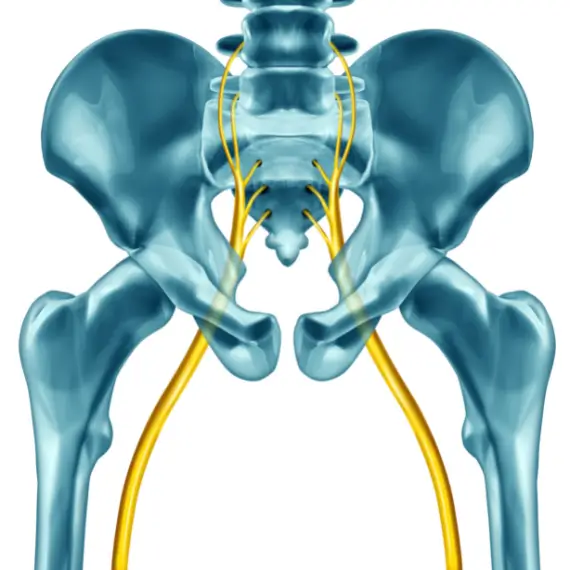

Your sciatic nerve is made up of several nerves from your lower lumbar and sacral spine at levels L4 through S3. These nerve roots fuse, forming a larger sciatic nerve in your pelvic cavity, and travel down behind your hamstring muscles. The nerve then splits into smaller nerve branches which cross into your calves and down toward the soles of your feet.